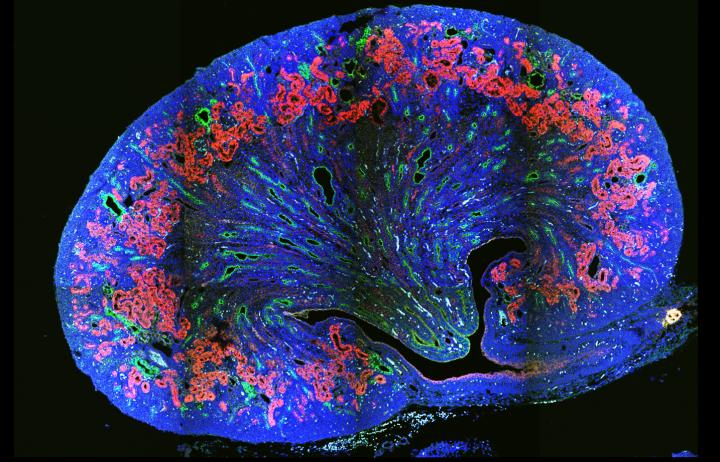

A new gene behind a rare form of inherited childhood kidney disease has been identified by a global research team.

University of Queensland researchers were part of the team that made the discovery that will improve genetic testing and could provide clues for future treatments for autosomal recessive polycystic kidney disease (ARPKD).

ARPKD causes enlarged kidneys, liver problems and high blood pressure, and often leads to renal failure in the 70 per cent of patients who survive the first weeks of life.

Using a technique called whole exome sequencing to analyse all of a patient's genes simultaneously, researchers in Germany and the US found errors in a gene called DZIP1L in four families with ARPKD.

Associate Professor Wicking and colleagues in Australia, Singapore and Germany used laboratory-based models to confirm that errors in this gene did indeed cause kidney defects, and began to explore and understand why.

"The gene DZIP1L appears to be related to the function of cilia, which are small antenna-like extensions that project from almost all cells of the body, including those in the kidney, and play an important role in controlling vital cellular functions," Associate Professor Wicking said.

"This gene makes a protein that acts at the base of the cilium, which, when faulty, causes a domino effect that leads to problems in cilia and, in turn, a malfunctioning kidney.